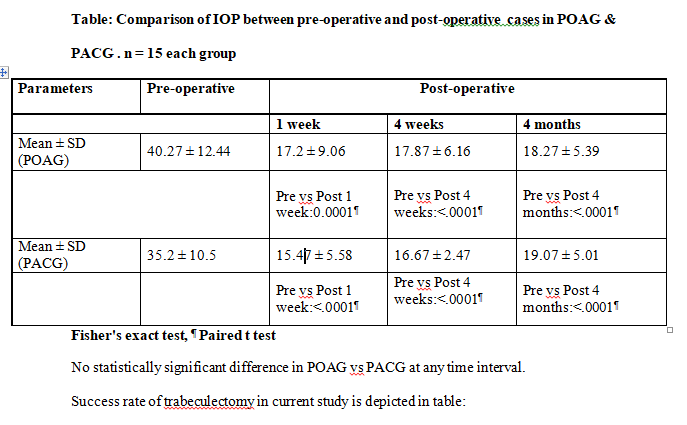

Comparison of trend of IOP in both groups is shown in table:

Post-surgery the reduction of IOP was similar for POAG at 17.9 ± 6.2 mmHg (4 weeks) and 18.3 ± 5.4 mmHg (4 months) and PACG group at 16.7 ± 2.5 (4 weeks) and 19.07 ± 5.01 mmHg (4 months). Maheshwari D et al, while studying

similar group over a 3-year period reported significant improvement in BCVA in ACG compared to OAG group, attributed to a higher number of cataract surgeries performed in the ACG group(9). Complete success was attained in 63.3%

patients and qualified success in 36.7%.

More POAG trabeculectomy were completely successful at 73.3% compared to 53.3% PACG cases, however the inter group difference was Not Significant. Maheshwari D et al have also reported higher success rates for trabeculectomy in